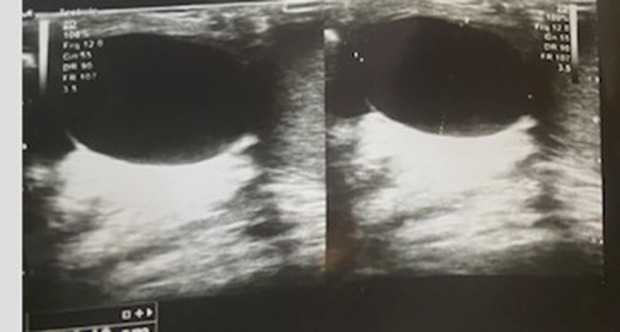

Case presentation: Here we report an unusual situation of testicular torsion induced by a large epididymal cyst in a young adult. The cyst was excised as well as bilateral testicular fixation and the patient was discharged on the third day. Clinical examinations and Doppler ultrasound at the sixth and twelfth postoperative weeks were both normal.